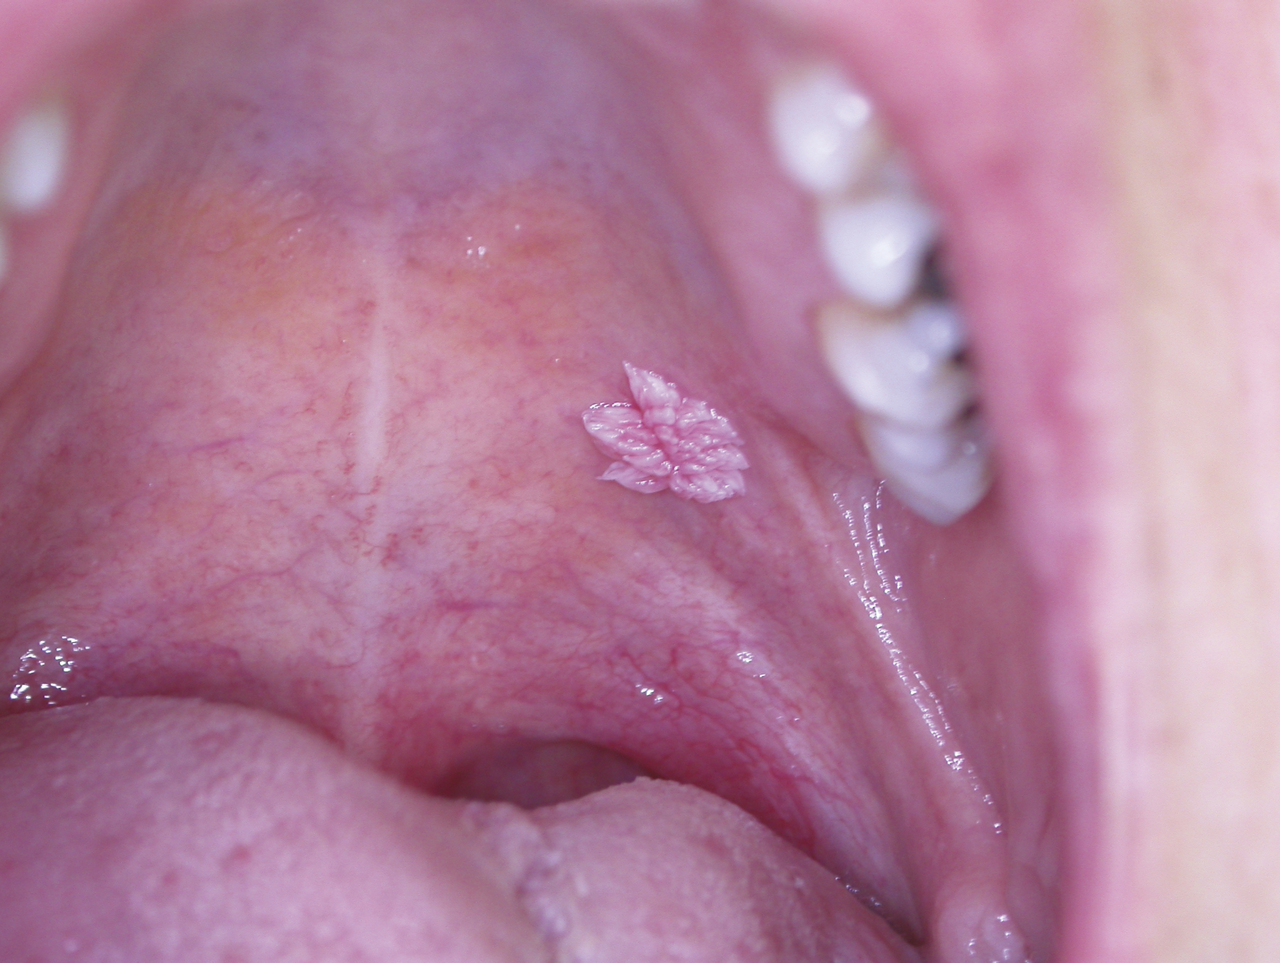

Enfin, les papillomes sont des élevures de quelques millimètres de diamètre, indolores à surface kératosique (fig. 6). La présence de papillomes multiples (fig. 7) fait rechercher une immunodépression.